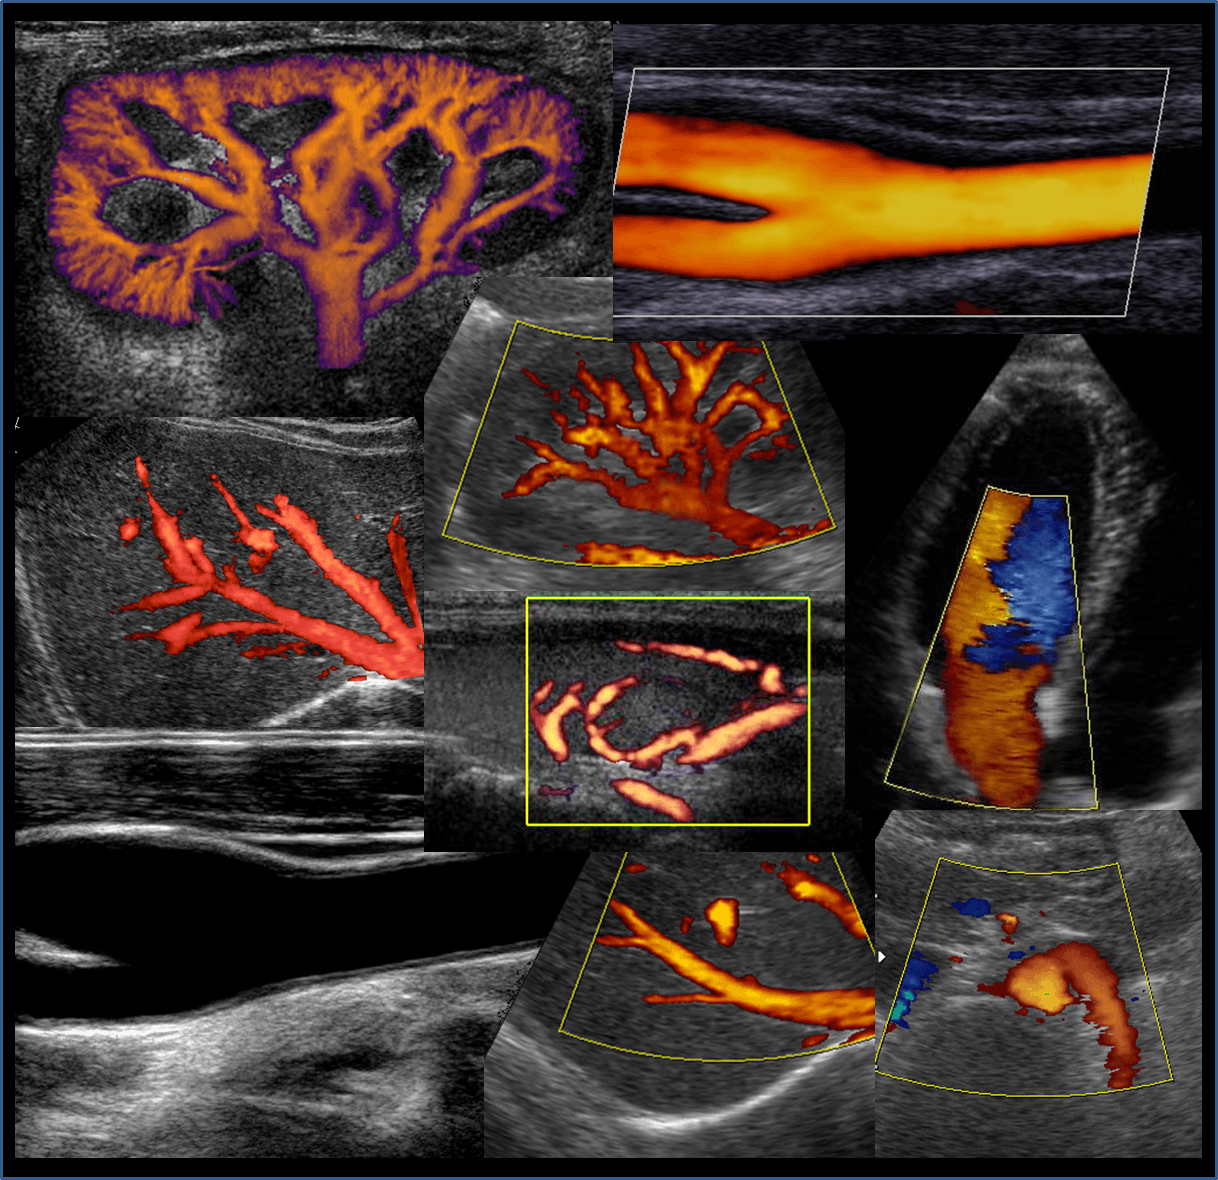

Grazie all'utilizzo delle più moderne apparecchiature del settore (tra cui Risonanza Magnetica a Livorno alto campo, RISONANZA MAGNETICA APERTA ad alta risoluzione, TAC 128 strati bassa dose, Mammografo Hologic 3D con tomosintesi oltre a Radiologia Digitale, MOC, Radiologia Odontoiatrica ed Ecografi di alta gamma) ed alla collaborazione di specialisti medici altamente qualificati, il Centro Sanitario è in grado di offrire una sempre più ampia gamma di servizi e prestazioni erogabili anche in regime convenzionato con il Servizio Sanitario Nazionale.